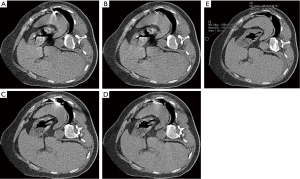

Subjective image quality evaluation

As differences in work arrangements and operators may lead to variation in the assessment of subjective image quality, the image quality evaluation in this study was carried out by two chest radiologists (with 3 and 5 years of experience, respectively), rather than by the intervention operators. The two radiologists were blinded to the study participants’ clinical information and performed the image quality evaluation independently. The overall image quality, including the visual region of interest (ROI) in the target lesion and the sharpness of the vessels in the proposed needle pathway, was assessed. The overall image quality was graded using a 5-point scoring system: 1 = unacceptable (poor definition of lesion and access), 2 = poor (borderline adequate lesion visualisation but inadequate visualisation of safe access, needle tip, or target area), 3 = adequate (adequate definition of lesion, access, and needle tip; slight impact of image noise), 4 = good (good visualisation of lesion, access, and needle tip; minimal image noise), and 5 = excellent (excellent definition of lesion, access, and needle tip). Scans with a quality score of 3–5 were considered to be acceptable (Figure 3A-3D).

Metal artefact evaluation

Metal artefacts were quantified using CT number reduction (CTNR) and metal diameter blurring (MDB) at the soft tissue window. The mean CT number of lesions was obtained using a 10-mm-diameter ROI at the lesions with the most obvious streak artefacts. The mean CT number over the ROI was measured using the pre-procedural CT scan (no metal) and a second scan that included metal (Figure 3E,3F). The CTNR was then calculated for each metal scan using the following equation: CTNR = HU (metal-image) – HU (baseline image). The outer needle was evaluated. The metal diameter accuracy was calculated from the image data by measuring the width of the needle profile at the cross-sections (Figure 3E) and comparing it to the true outer diameter of the actual needle (16,17) using the following equation: MDB = (Width (image)−Width (true)/Width (true)). Lower values for CTNR and MDB indicate fewer artefacts and higher image quality.

The qualitative image quality assessment scores given by both readers were significantly higher for the tin filter groups than for the routine-dose groups (group A vs. group C, P=0.03; group B vs. group D, P=0.188; Table 3). These scores showed excellent interobserver agreement (κ=0.87–0.94 for each group; Table 4).

The scores for images with iMAR were higher than those without iMAR (group A vs. group B, or group C vs. group D, adjusted P<0.01), which suggested that the qualitative image quality of CT with iMAR was superior to that without iMAR (Figures 2,3).

The objective image quality results are summarised in Table 3 and visualised in Figure 4. In the dose-related image analysis, the mean image noise in the tin filter groups was higher than that in the routine-dose groups (group A vs. group C, and group B vs. group D, all P<0.05). The mean CNR in the tin filter groups was lower than that in the routine-dose groups, while the mean FOM was higher in the tin filter groups than in the routine-dose groups (group A vs. group C, or group B vs. group D; all P<0.05).

The metal diameter blurring (MDB) values in the tin filter groups with and without iMAR were 0.85 and 2.26, respectively (P<0.01, Table 3 and Figure 4), with a true needle width of 1.4 mm; for the routine-dose groups, the metal diameter blurring (MDB) values were 1.25 and 3.97 with and without iMAR, respectively (P<0.01). The CT number reduction (CTNR) values in the tin filter group with and without iMAR were 116.62 and 158.10 HU, respectively (P<0.01); for the routine-dose groups, the CTNR values were 147.55 and 246.51 HU with and without iMAR, respectively (P<0.01). In images without iMAR reconstruction, the tin filter group was slightly superior to the routine-dose group (P=0.017). The ICC for the CTNR and MDB in all groups showed excellent agreement (Table 4).